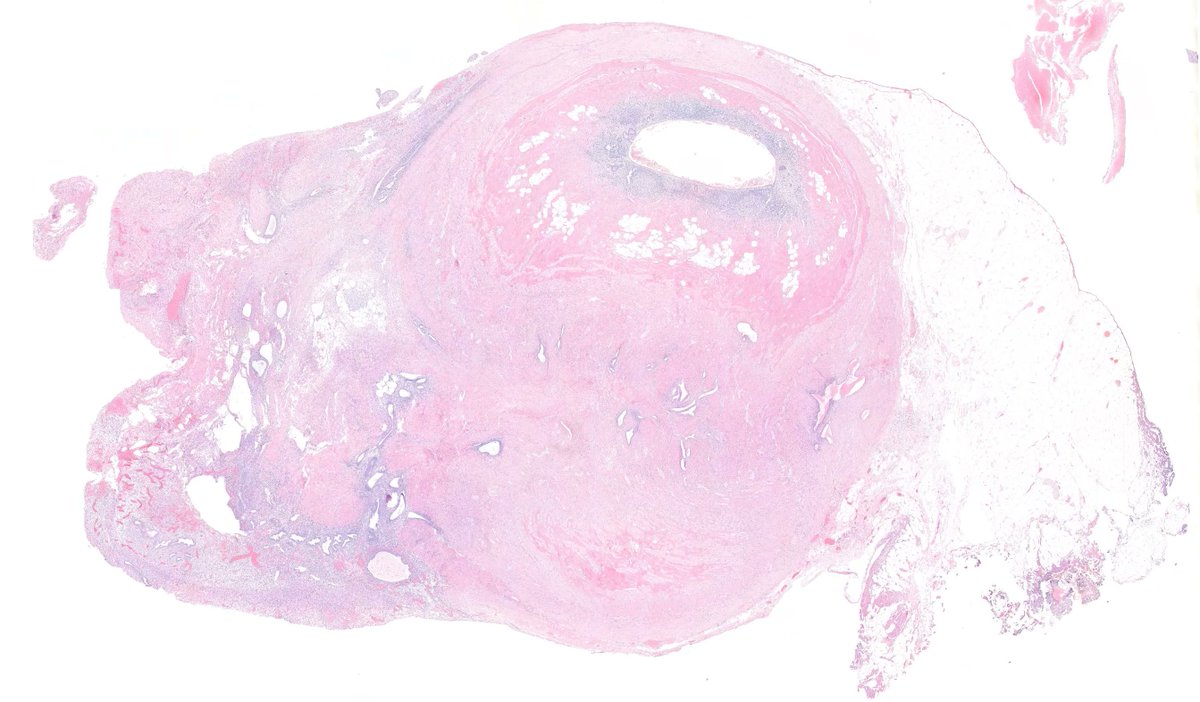

Appendiceal endometriosis. Typically incidental but can cause pain, obstruction or diarrhea. #GIpath

Typically incidental but can cause pain, obstruction or diarrhea. #GIpath